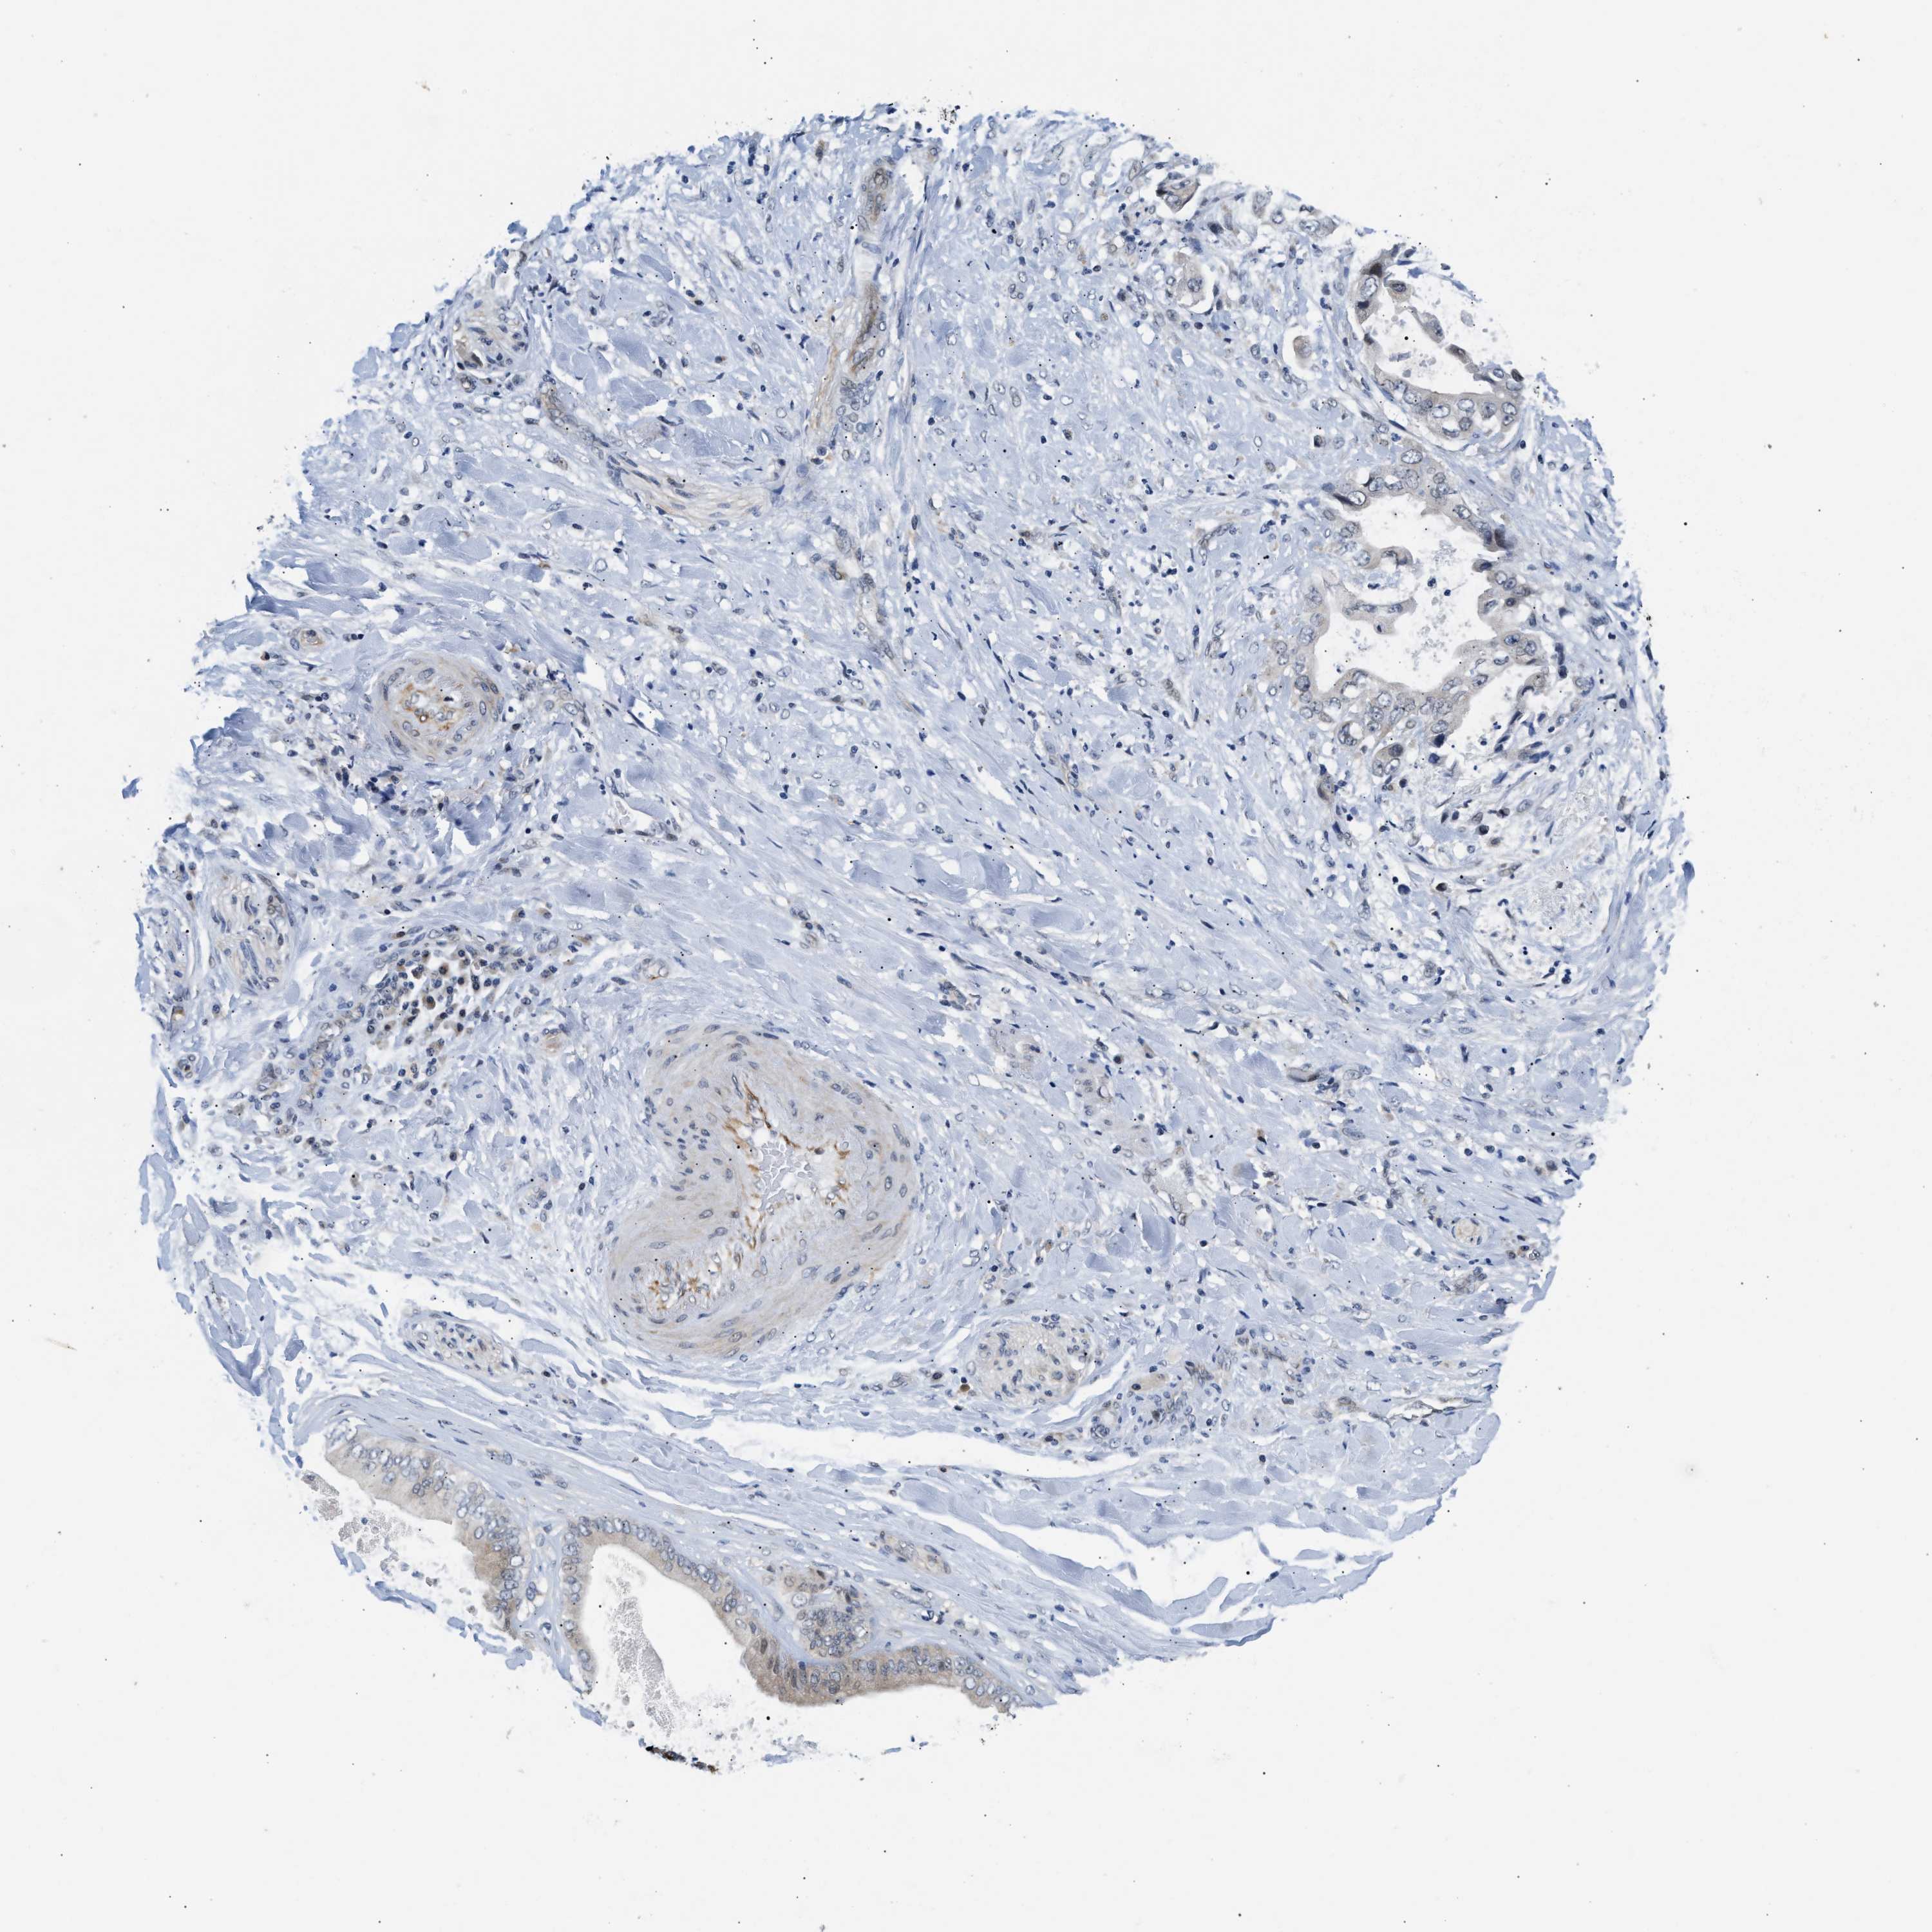

LIVER CANCER - Protein expressioni

A mouse-over function shows sample information and annotation data. Click on an image to view it in a full screen mode. Samples can be filtered based on level of antibody staining by selecting one or several of the following categories: high, medium, low and not detected. The assay and annotation is described here.

Note that samples used for immunohistochemistry by the Human Protein Atlas do not correspond to samples in the TCGA dataset.

Antibody stainingi

Antibody staining in the annotated cell types in the current human tissue is reported as not detected, low, medium, or high, based on conventional immunohistochemistry profiling in selected tissues. This score is based on the combination of the staining intensity and fraction of stained cells.

Each image is clickable and will lead to virtual microscopy that enables deeper exploration of all samples and also displays staining intensity scores, fraction scores and subcellular localization as well as patient and tissue information for each sample.

Antibody HPA044244

Antibody HPA058777

Antibody CAB020694

Staining

High

Medium

Low

Not detected

Intensity

Strong

Moderate

Weak

Negative

Quantity

>75%

75%-25%

<25%

None

Location

Nuclear

Cytoplasmic/membranous

Cytoplasmic/membranous,nuclear

Cholangiocarcinoma

Carcinoma, Hepatocellular, NOS